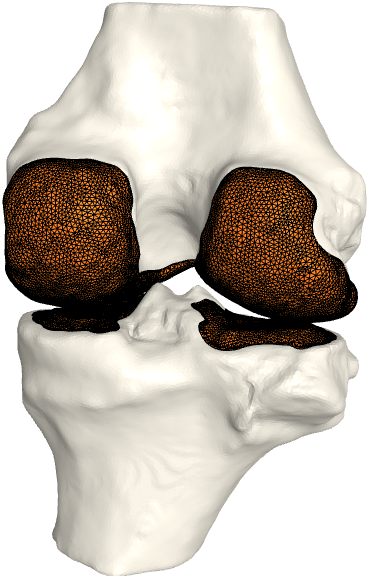

The FE analysis results show that the generated models produce smooth stress patterns in a pseudo stance without any geometry-related convergence issues. As mentioned in section 4, these results only serve as a verification test of simulation properties. We need a more advanced simulation setting to model a real stance position. We leave this for future work. Moreover, we believe that minor modifications will estimate the shoulder joint cartilage since it has a similar ball-in-socket structure. Fig. 5 shows early evidence of generalization. In contrast, other joints, such as the knee joint, are challenging. We leave other joint types for future work.

Refer to caption

(a)

(b)

(c)

Figure 5: a) All generated cartilages. Zoom boxes highlight the pubic and sacroiliac joint cartilages. b) Shoulder joint cartilage c) Femoral and tibial cartilage in the knee joint. Bone models are acquired from available datasets [3, 5, 4].